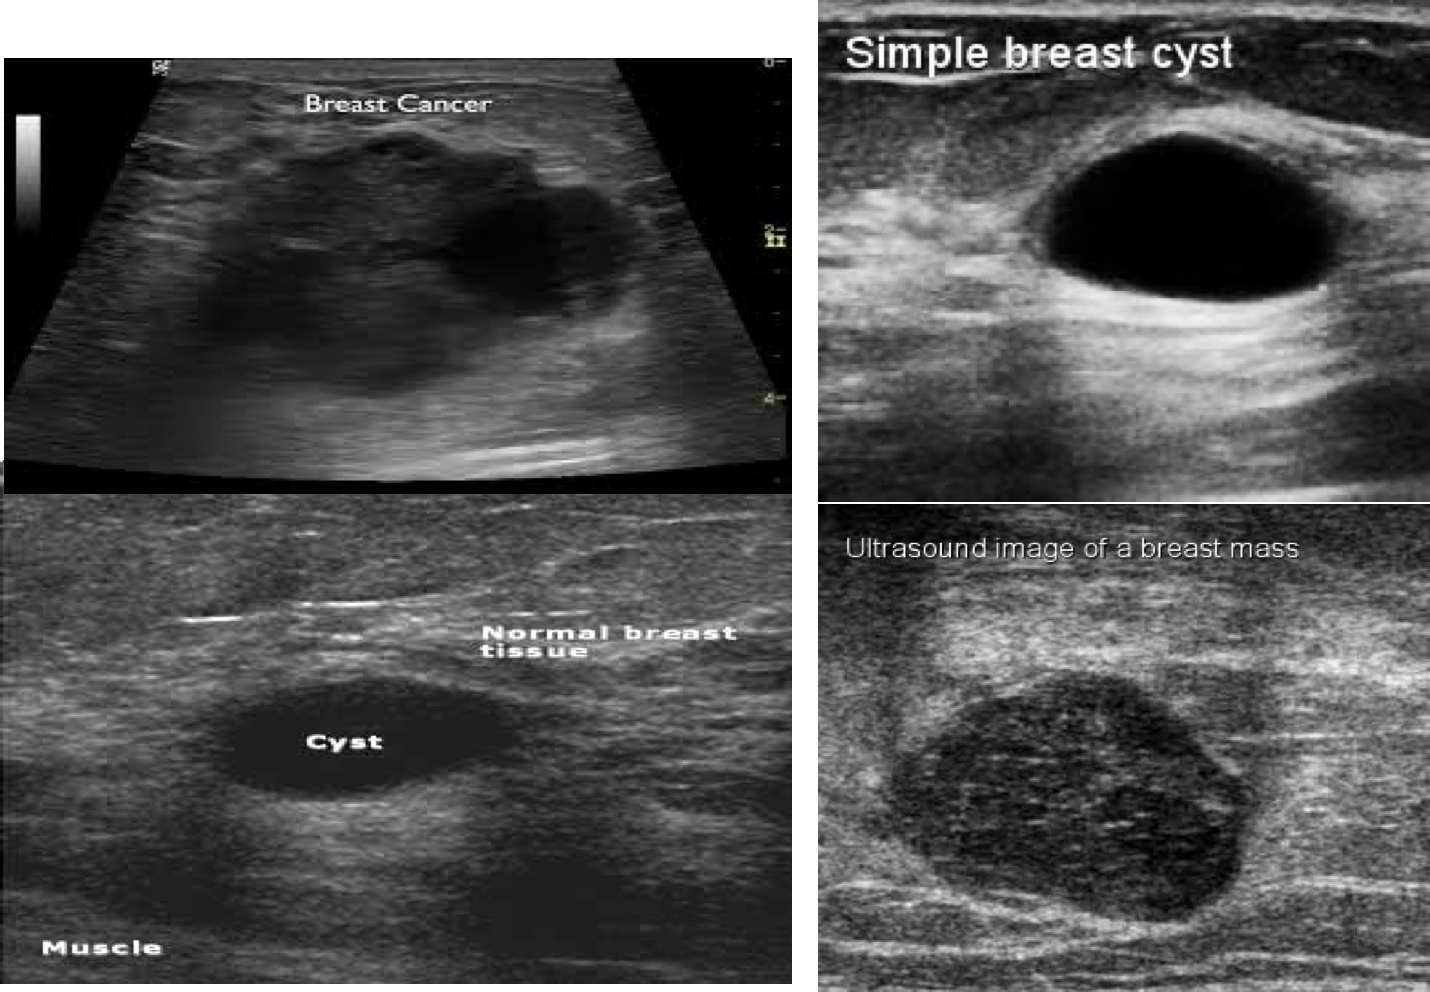

Ultrasound image of a benign breast lesion. There is a very well-defined hypoechoic ovoid mass typical of a benign fibroadenoma.

Breast Ultrasound is usually done to differentiate between solid and cystic masses